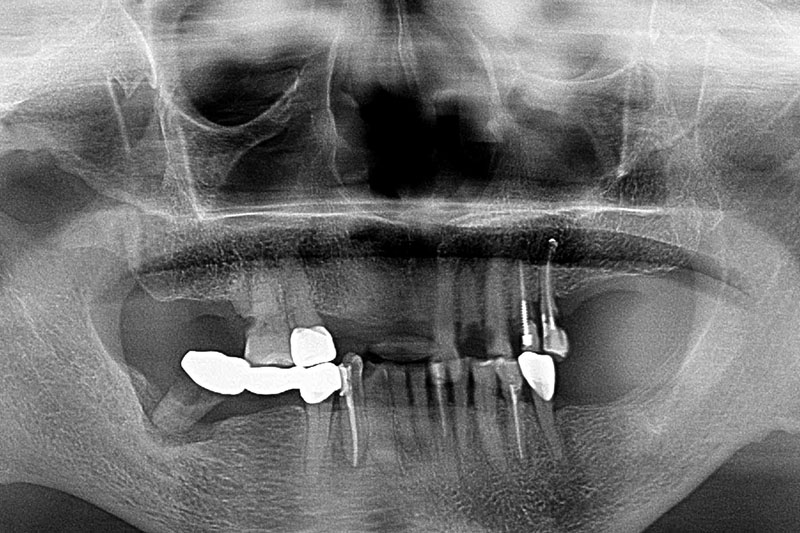

鼻竇增高術-全口X光攝影

案例一

術前